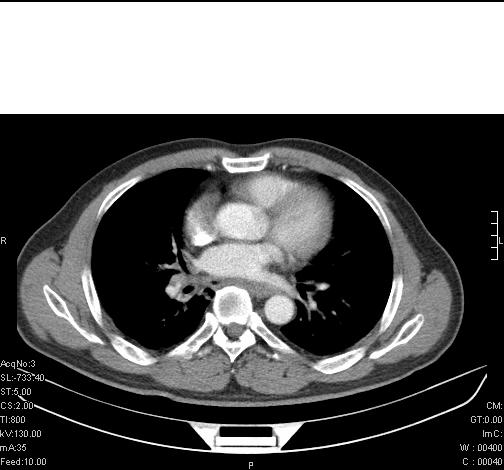

前几天,发了患者的平扫片,患者抗炎一周后增强扫描。右中叶病灶吸收明显,但下叶病灶未见明显吸收。右肺门可见结节影,看来凶多吉少

右肺下叶支气管管腔狭窄,管壁增厚,右下肺见斑片状高密度影,考虑右侧肺门中心肺癌伴阻塞性肺炎

右肺下叶支气管壁不规则增厚,右肺下叶有斑片状影分布。考虑右肺中央型肺癌伴右肺下叶阻塞性改变。建议支纤镜检查。平扫比增强较好显示了病变情况。

右主支气管狭窄,管壁增厚。考虑右中心性肺ca伴阻塞性肺炎。

既然抗炎治疗有效,可继续治疗;右肺下叶支气管管腔狭窄,管壁增厚,右下肺见斑片状高密度影,右侧主支气管后见结节影(淋巴结?),肺癌不能排出。